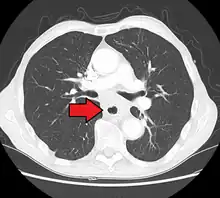

Additional testing is needed to assess how much the cancer has spread (see § Staging, below). Computed tomography (CT) of the chest, abdomen and pelvis can evaluate whether the cancer has spread to adjacent tissues or distant organs (especially liver and lymph nodes). The sensitivity of a CT scan is limited by its ability to detect masses (e.g. enlarged lymph nodes or involved organs) generally larger than 1 cm.[43][44] Positron emission tomography is also used to estimate the extent of the disease and is regarded as more precise than CT alone.[45] PET/MR as a novel modality has shown promising results in preoperative staging with fair feasibility and good correlation in comparison to PET/CT. It can enhance tissue differentiation with lowering the radiation dose to the patient.[46] Esophageal endoscopic ultrasound can provide staging information regarding the level of tumor invasion, and possible spread to regional lymph nodes.

Contrast CT scan showing an esophageal tumor (coronal view)